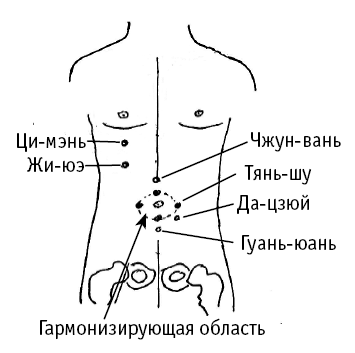

Жи-юэ («солнце-луна») расположена прямо вниз от соска, в 7 межреберном промежутке.

Ци-мэнь («оборот – ворота») расположена на 1 ребро выше (по вертикали) от точки Жи-юэ.

Чжун-вань («середина эпигастрия»), которая расположена на передней срединной линии, на 4 цуня выше пупка.

Тянь-шу («стержень неба») распложена на 2 цуня кнаружи от пупка.

Да-цзюй («самый большой») расположена на самой высокой точке живота (отсюда и название), на 2 цуня кнаружи и на 2 цуня ниже пупка.

Гуань-юань («ключ к первичной энергии») расположена на срединной линии живота, на 3 цуня ниже пупка.